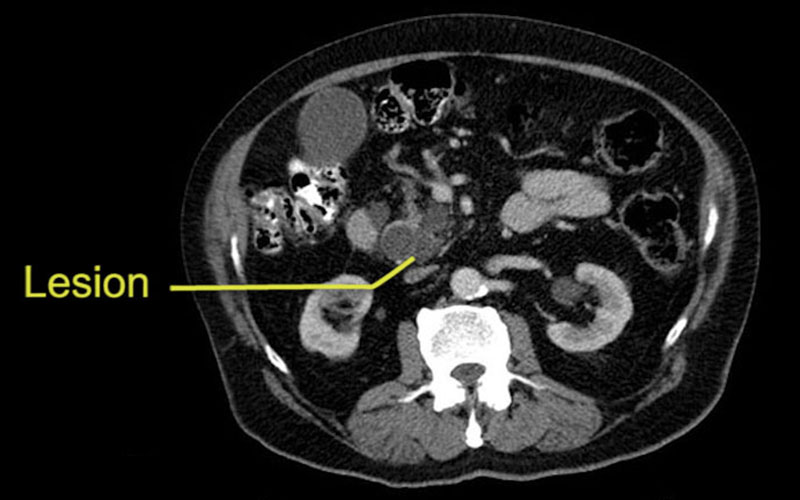

An 83-year old man presented with painless jaundice. On ERCP he was found to have an ampullary lesion, a biopsy-proven adenocarcinoma. His initial bilirubin level was in the 400s, but returned to normal levels after he was stented pre-operatively. Our plan is to prepare him for a Whipple operation (pancreaticoduodenectomy).